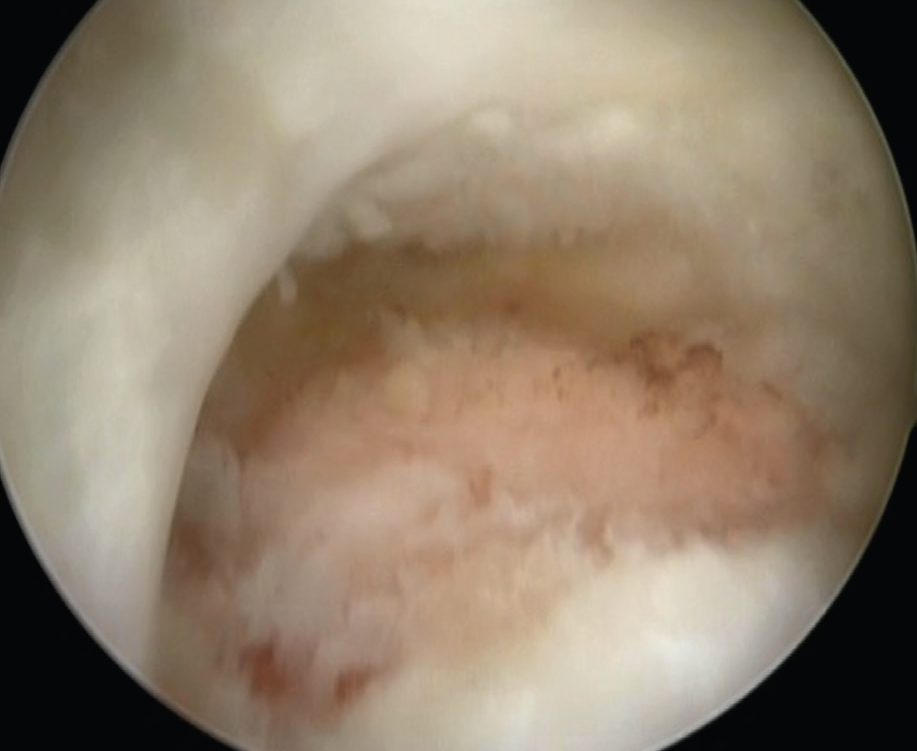

Artroskopik Tendon Onarımı: Bu işlemde, yırtık tendon kemiğe kamera (artroskop) yardımıyla ve küçük kesilerden el aletleri sokularak tespit edilir. Artroskopik cerrahide kamera sistemi ile elde edilen görüntüler yüksek kalite ve çözünürlükte olduğu için açık ameliyatta görülemeyen tüm detaylar monitörden izlenebilir.

![]() |

| A. Rotator manşet yırtığının artroskopik görüntüsü, B. Yırtığın artroskopik tamiri | |